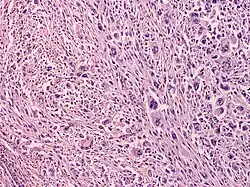

Atypical fibroxanthoma (AFX) is frequently found to have a well-circumscribed, nonencapsulated dermal tumor that is either contiguous with the epidermis or separated from it by a narrow zone of collagen (Grenz zone); plump spindle cells with prominent nuclei, epithelioid cells, and multinucleated giant cells; atypical mitoses and severe cellular pleomorphism; and varying presence of thin or ulcerated epidermis or peripheral epidermal collarette.[9]